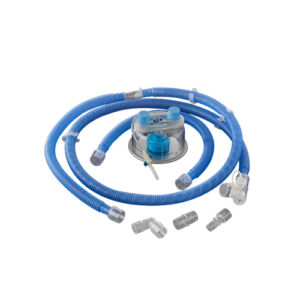

BC 630

Adult Breathing Circuit with Heated Wire for High Flow Oxygen Therapy